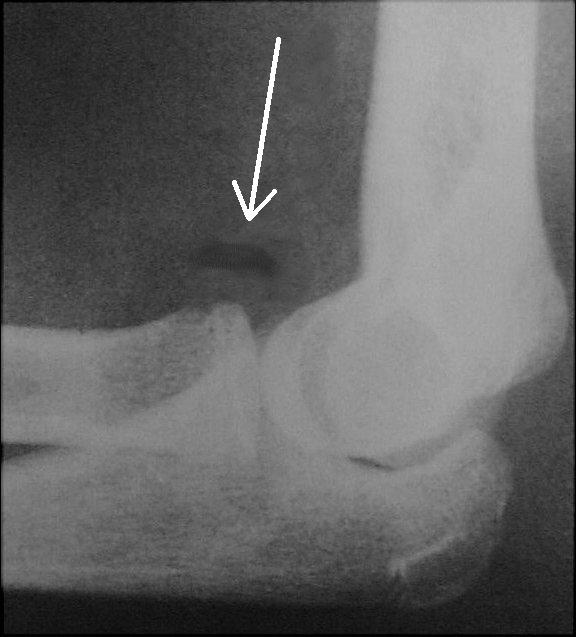

A lateral view of the elbow in a boy reveals a lipohemarthrosis. The fracture site is not visible. The anterior fat pad is not displaced.